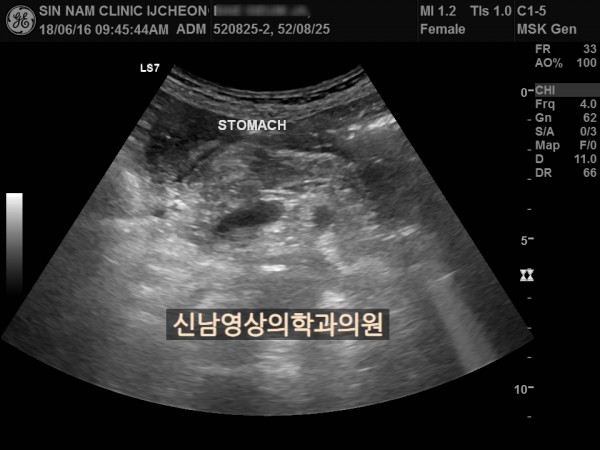

본 환자분은 변비가 지속되면서 좌하복부 통증이 있으셨던 분으로 본원에서 복부 초음파 검사를 진행하였습니다.

하행 결장 부위에서 장이 두꺼워진 소견이 보여 진행된 대장암의 가능성이 농후해보여 대학병원으로 전원해 대장내시경을 받고, 수술로 2기암으로 진단되신 케이스입니다.

위암이나 대장암은 점막에서 발생하는 0기암은 초음파로 진단할 수 없지만 대장암이 점막을 넘어 근육층이나 장간막으로 퍼지게 되면 초음파 검사상 근육, 장간막 부위가 두꺼워지는 소견으로 나타나 발견하기도 합니다.